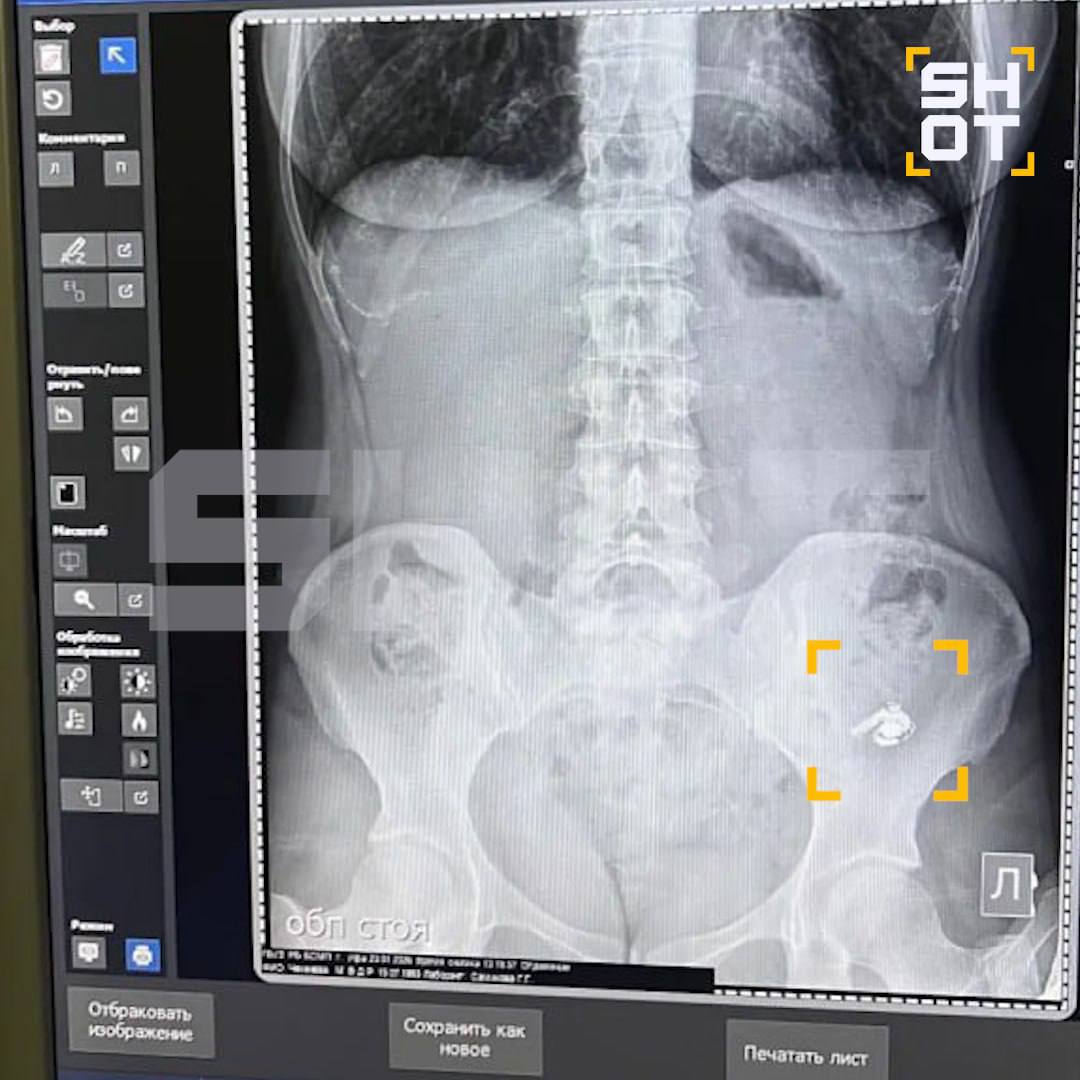

AirPods пролежал в ее желудке около суток. В больнице на рентгене подтвердили, что наушник внутри, но доставать его не стали — врачи посоветовали ждать, пока он выйдет естественным путем.